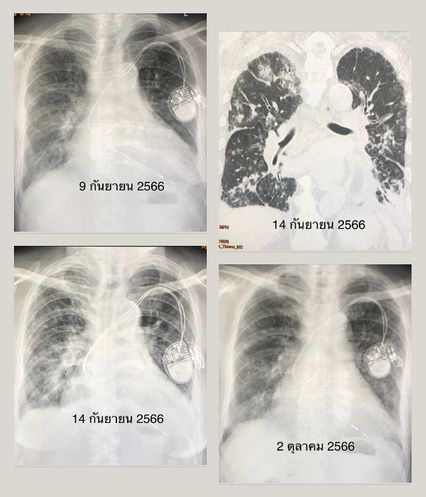

ต่อมาวันที่ 6 ก.ย.66 ผู้ป่วยมีไข้ ไอ เจ็บคอ มีน้ำมูก ตรวจแยงจมูกพบไวรัสไข้หวัดใหญ่สายพันธุ์ A ได้ยา Oseltamivir (โอเซลทามิเวียร์) 75 มิลลิกรัม กินที่บ้าน เช้า-เย็น คนไข้กินยาไปได้ 2 วันครึ่ง อาการไม่ดีขึ้น ยังมีไข้ ไอ เริ่มเหนื่อยเดินไม่ได้ และเท้าบวม 2 ข้าง จึงกลับมาพบแพทย์ที่โรงพยาบาล ในวันที่ 9 ก.ย.66 ตรวจร่างกาย อุณหภูมิ 38.3 องศาเซลเซียส ระดับออกซิเจนที่ปลายนิ้วต่ำ 91% ฟังปอดมีเสียงกรอบแกรบ ที่ชายปอดทั้ง 2 ข้าง เท้าบวม 2 ข้าง เอกซเรย์ปอด หัวใจโต มีฝ้าขาว น้ำในเยื่อหุ้มปอดเล็กน้อยทั้ง 2 ข้าง

วันที่ 14 ก.ย.66 ติดตามเอกซเรย์ปอดและเอกซเรย์คอมพิวเตอร์ปอด ยังเห็นมีฝ้าขาวกระจายในปอดมากขึ้นและมีน้ำในเยื่อหุ้มปอดทั้ง 2 ข้าง ผู้ป่วยนอนรักษาในโรงพยาบาลนาน 16 วัน ไข้ลง อาการค่อยๆ ดีขึ้น ก่อนกลับบ้านไม่ไอ ไม่เหนื่อย เท้าที่บวมยุบลง เดินได้ ไม่ต้องใช้ออกซิเจน เอกซเรย์ปอดดีขึ้นช้าๆ คนไข้กลับมาตรวจอีกครั้งวันนี้ (2 ต.ค.66) น้ำหนักลด 5 กิโลกรัม ไม่บวม ไม่มีไข้ ไม่ไอ ไม่เหนื่อย ระดับออกซิเจนที่ปลายนิ้ว 95%  เอกซเรย์ปอดดีขึ้นมาก